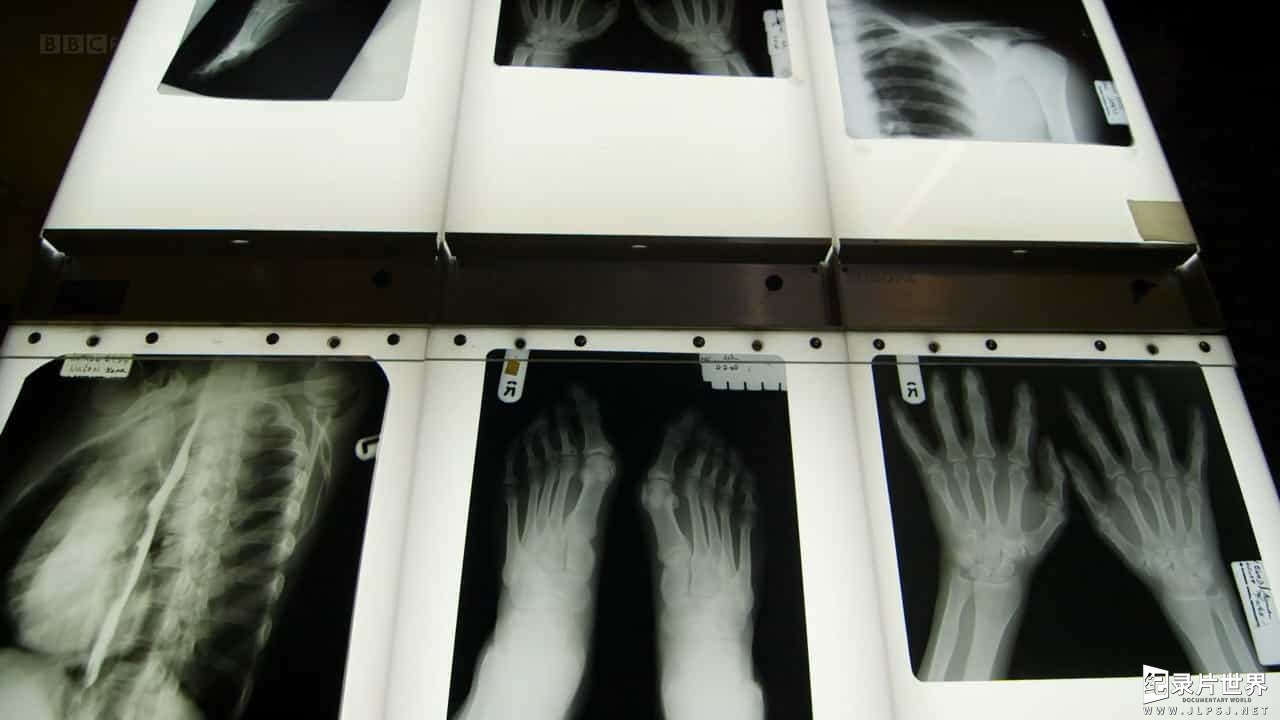

人的手和脚进化为精巧复杂的结构。George McGavin博士在解剖专家的配合下,详尽展示手足的各部分结构和功能。